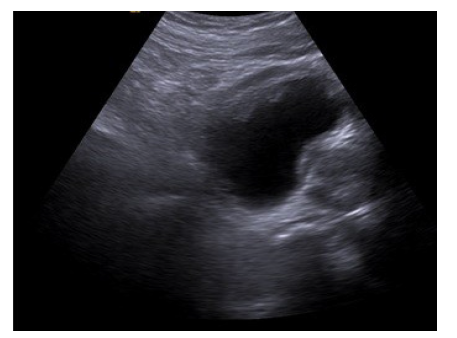

A 64-year-old male presented to our department with complaints of poor urinary stream, frequency, and dysuria. He had no known medical comorbidities. Urinalysis revealed pyuria, microscopic haematuria and positive nitrites. He was initially started with antibiotics and ultrasonography was ordered, which revealed focal, polypoidal, irregular wall thickening of the anterior wall of bladder with prostatomegaly and median lobe hypertrophy (Figure 1).